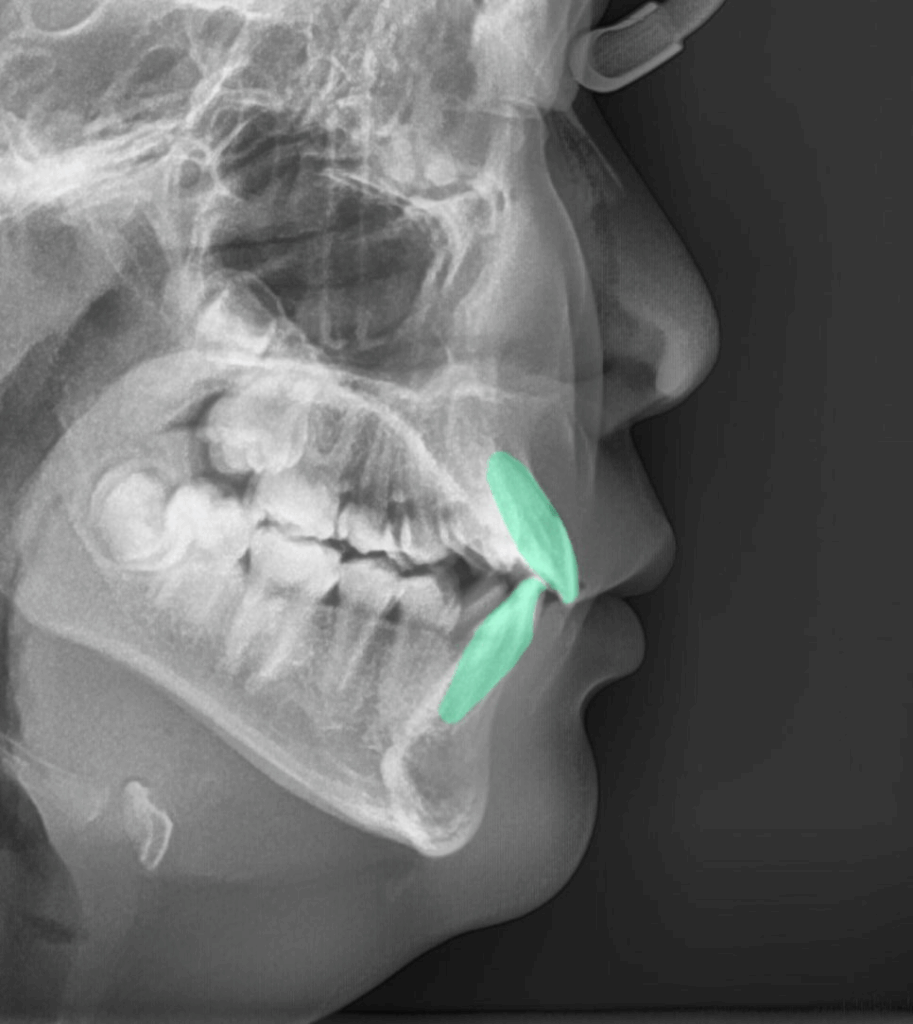

| 5. 언제 치료를 시작하는 것이 좋을까요?

같이 검사할 수 있는 수완부 엑스레이 촬영(성장기 검사)

23.08.17

아이들의 경우 성장기에

치료를 시작하는 것이 효과적입니다.

심한 부정교합이나 틀어짐이 아니라면

성인도 비교적 짧은 기간 내에

좋은 결과를 얻을 수 있습니다.

중요한 것은 하루라도

빨리 정확한 진단을 받아보시는 것인데요.

구치 배열이나 다른 문제들도

같이 확인해야 알맞은 치료 계획을

세울 수 있기 때문입니다.